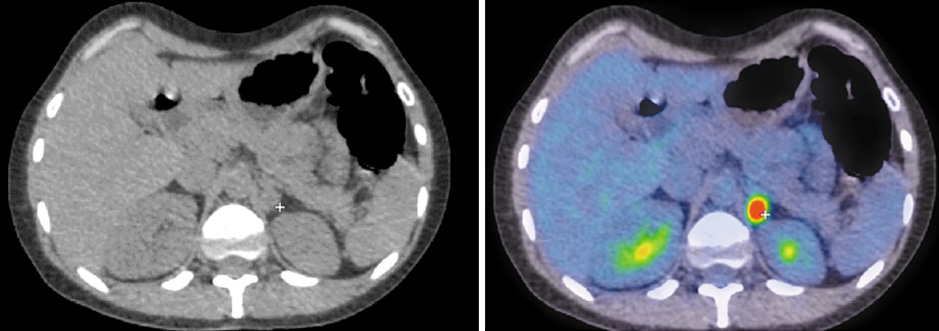

В медиальной ножке левого надпочечника имеется образование размером 16×13 мм с фиксацией 18F-ФДГ, SUVmax – 8,78 (рис. 2). Кроме того, выявлены множественные очаги патологической фиксации РФП на фоне литической перестройки костной ткани в грудинных концах ключиц, грудине, крыле левой и правой подвздошных костей, грудных позвонках, головке правой плечевой кости и большом вертеле левой бедренной кости.

Рис. 2. Пациентка Б., 41 год. ПЭТ/КТ с 18F-ФДГ до начала лечения. На аксиальных КТ- и ПЭТ/КТ-проекциях определяется образование медиальной ножки левого надпочечника размером 16×13 мм с фиксацией РФП, SUVmax – 8,78. / Fig. 2. Female patient B., 41 years old. PET/CT with 18F-FDG before the treatment. Axial CT and PET/CT views reveal a mass of the left adrenal gland medial limb of 16×13 mm with a radiopharmaceutical uptake with SUVmax of 8.78.

Рис. 4. Пациентка Б., 41 год. ПЭТ/КТ с 18F-ФДГ по окончании 6 циклов полихимиотерапии. На аксиальных КТ- и ПЭТ/КТ-проекциях образование в области медиальной ножки левого надпочечника не определяется, регрессировало. / Fig. 4. Female patient B., 41 years old. PET/CT with 18F-FDG at the end of 6 cycles of polychemotherapy. Axial CT and PET/CT views showed no mass in the area of the left adrenal gland medial limb; the mass regressed.